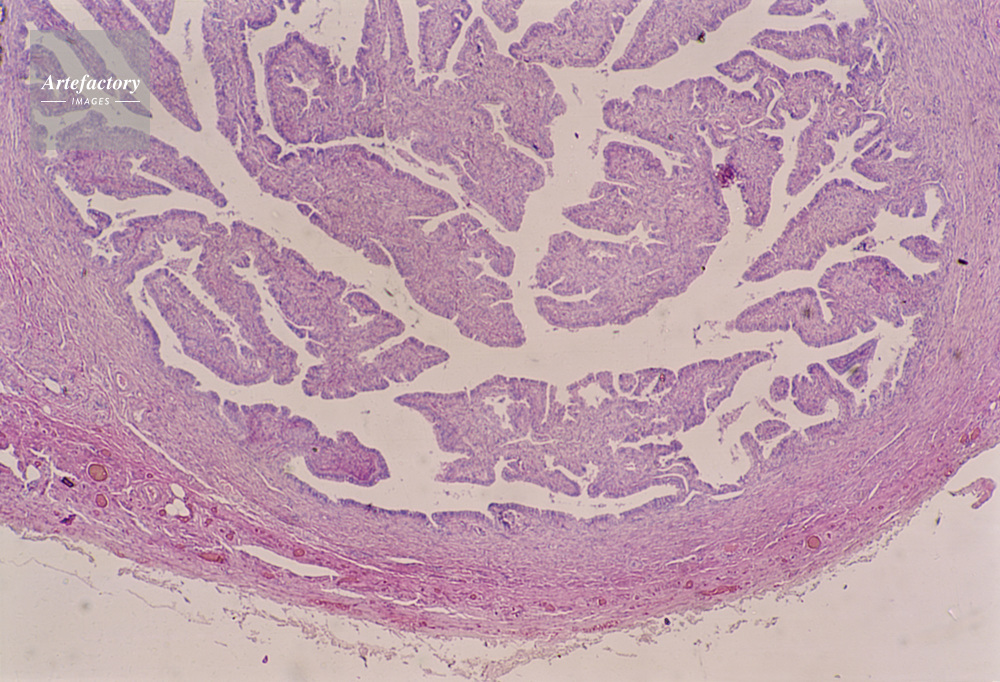

| キャプション | 繊毛上皮,輸卵管,20倍,人間 | 制限事項 | ||